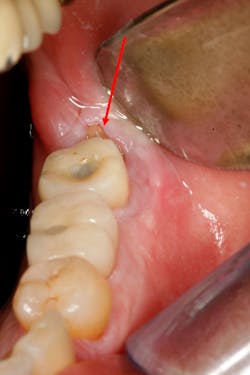

Failures and complications associated with bone augmentation can have a devastating effect on the outcome of dental implant treatment. These complications are classified as either early or late. Early complications include wound dehiscence, membrane and graft exposure, and infection, with the most common complication being wound dehiscence (figures 1a–1c). A strong correlation has been shown between flap tension and wound dehiscence, with wound breakdown occurring in 40% of cases where the flap tension reached 40.1 N as opposed to 10% for flap tensions < 0.1 N.1

Figures 1a–1c: Wound dehiscence occurring after bone augmentation procedures.